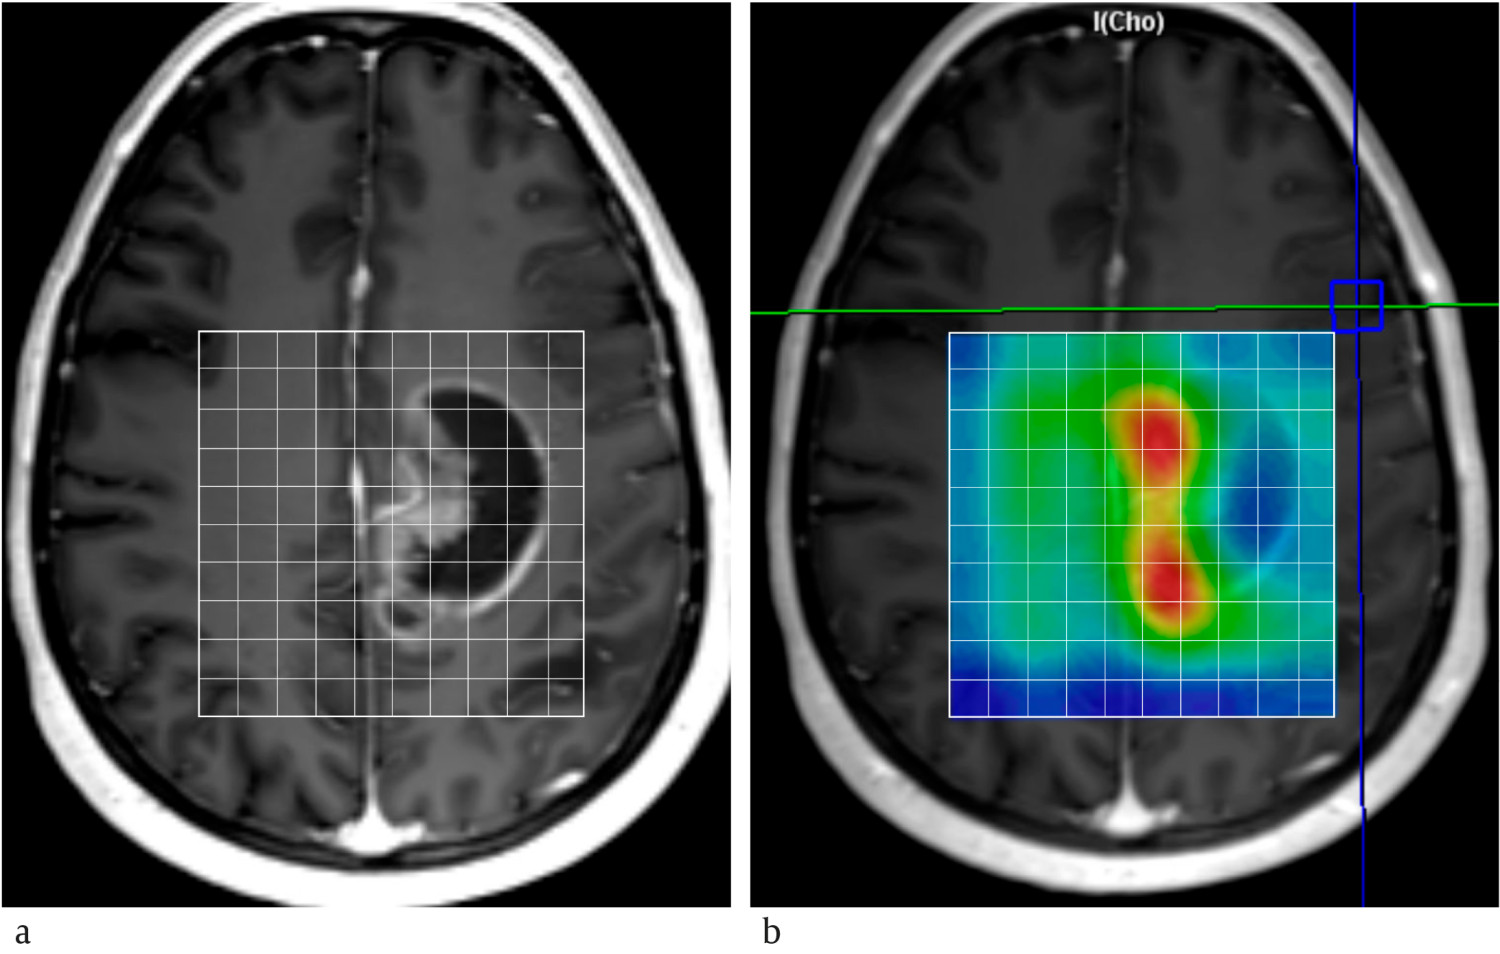

Hvert år diagnostiseres omtrent 300 pasienter i Norge med malign primær hjernesvulst, hvorav rundt 250 er høygradige gliomer (8). MR-spektroskopi kan bidra til å skille mellom hjernesvulst og andre typer lesjoner som abscess og subakutt infarkt (9). Generelt har hjernesvulster forhøyet mengde kolin, laktat og mobile lipider samt redusert mengde N-acetylaspartat og kreatin sammenlignet med tilsvarende normalt vev. Kolinmengden øker med malignitetsgraden, og forholdet mellom kolin og kreatin, og mellom kolin og N-acetylaspartat, er signifikant høyere i høygradige enn i lavgradige gliomer (figur 2) (10). Laktat og mobile lipider kan påvises i glioblastomer, men er også vanlig i metastaser.

Høygradige gliomer behandles vanligvis med kirurgi etterfulgt av radiokjemoterapi. Radiokjemoterapi kan føre til ødem med kontrastopptak i operasjonsområdet, såkalt pseudoprogresjon. Dette er vanskelig å skille fra reell tumorprogresjon på MR-bilder, men MR-spektroskopi kan bidra til å differensiere tumorvekst fra strålereaksjon og pseudoprogresjon. Typisk viser et MR-spekter ved tumorprogresjon høye mengder kolin, mens områder med pseudoprogresjon viser laktat og mobile lipider som tegn på nekrose. MR-spektroskopi brukt i tillegg til MR-diffusjon er vist å kunne øke nøyaktigheten i diskriminering mellom pseudoprogresjon og reell tumorprogresjon (11). Som selvstendig modalitet har MR-spektroskopi moderat nøyaktighet i tumordiagnostikk, men kan være verdifull i kombinasjon med MR-avbildning (9).

Vi opplever at forventningene til MR-spektroskopi i klinisk praksis igjen er stigende. Dette skjer av to årsaker. Den ene er økt utbredelse av MR-skannere med høy feltstyrke (3 og 7 tesla). Høyere feltstyrke muliggjør deteksjon av metabolitter med lav konsentrasjon og differensiering av topper som overlapper ved lavere feltstyrke. Kjemisk skift-avbildning kan være en aktuell teknikk for å få til dette (figur 3). Metoden utføres over flere volumer, typisk 1 cm3, dekker et helt snitt eller volum av hjernen, og inneholder informasjon om regionale variasjoner i metabolittmengder. Ved St. Olavs hospital brukes denne teknikken ved omtrent halvparten av MR-spektroskopiundersøkelsene av hjernesvulster.